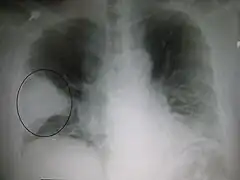

Enfermedades del pulmón

Las enfermedades del pulmón pueden ser congénitas (presentes desde el nacimiento) o desarrollarse a lo largo de la vida. Algunas de las más frecuentes son la enfermedad pulmonar obstructiva crónica o EPOC, causada mayoritariamente por la inhalación del humo de tabaco, el asma bronquial provocado frecuentemente por alergia al polen u otras sustancias, la neumonía y bronconeumonía debida a la proliferación de bacterias o virus patógenos en los alveolos pulmonares, el cáncer de pulmón también muy relacionado con el tabaquismo y la tuberculosis pulmonar muy frecuente en determinados países y asociada tradicionalmente a la desnutrición, la pobreza, hacinamiento y malas condiciones de vida. A continuación una lista incompleta de algunas enfermedades del pulmón:[9][10]

- Cáncer de pulmón: Es una de las enfermedades pulmonares más graves y uno de los cánceres con mayor incidencia en el ser humano. En función de la apariencia de las células cancerosas, puede distinguirse entre cáncer de pulmón microcrítico y cáncer de pulmón no microcrítico. El primero recibe también el nombre de cáncer de células en grano de avena, su nivel de incidencia representa entre un 10 y un 15 % del total de cánceres de pulmón diagnosticados. El no microcítico se divide, a su vez, en adenocarcinoma, carcinoma de células escamosas y carcinoma de células grandes. Otros tipos de tumores malignos en los pulmones son los tumores carcinoides, linfomas y sarcomas. El tabaco es el factor de riesgo más importante a la hora de sufrir un cáncer de pulmón, motivando hasta un 80 % de las muertes por esta enfermedad.[12]

- Neumonía y bronconeumonía: La inflamación generalmente de origen infeccioso afecta a los alveolos pulmonares. Las neumonías y bronconeumonías han sido durante muchos siglos la causa de mortalidad más importante entre niños y ancianos. En la actualidad son un problema muy grave estadísticamente, y gran parte de la mortalidad senil se debe a ello.

- Neumotórax: Se produce por la entrada de aire al espacio pleural, causando un colapso pulmonar. Algunos síntomas son dolor agudo en el pecho y sensación de asfixia.

- Tuberculosis: Se trata de una enfermedad infecto-contagiosa que se suele contagiar por vía aérea, está provocada por el mycobacterium tuberculosis.